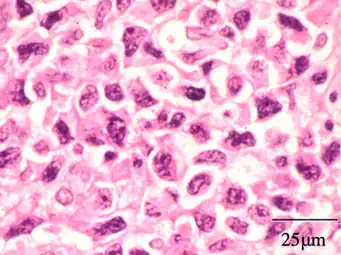

Histopathology of sinonasal contents removed from surgery can be diagnostically valuable:

Benign chronic mixed inflammation of an inflammatory sinonasal polyp

Acute inflammation characterized by neutrophils

Extranodal NK/T cell lymphoma, nasal type.[103] It may be incidentally discovered in people undergoing surgery for sinusitis.[104]